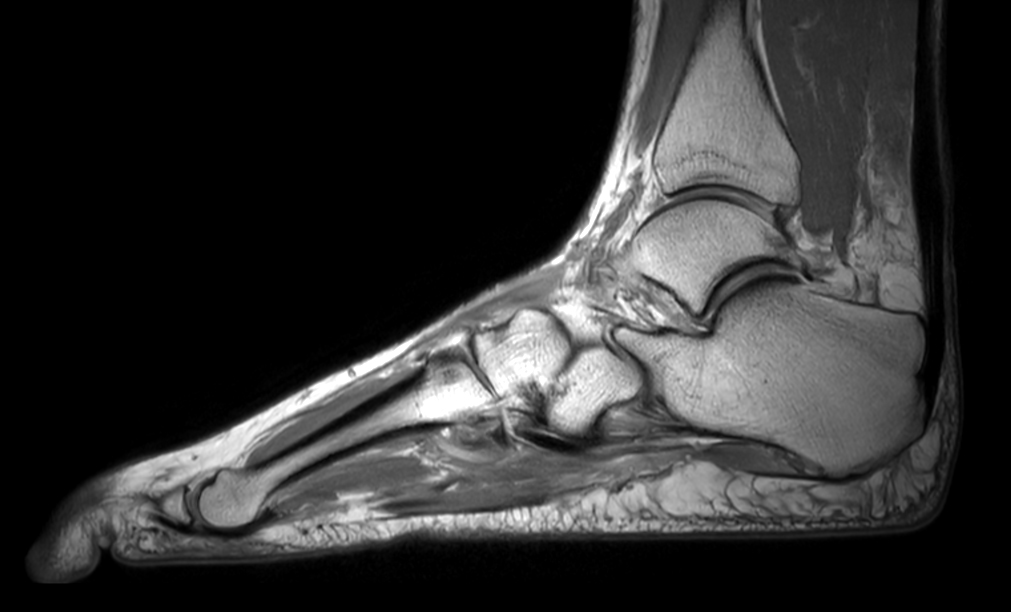

Imaging with the dS 16ch FootAnkle coil

General Hospital Sint Blasius, Dendermonde, Belgium

Patient who was referred for imaging of the achilles tendon